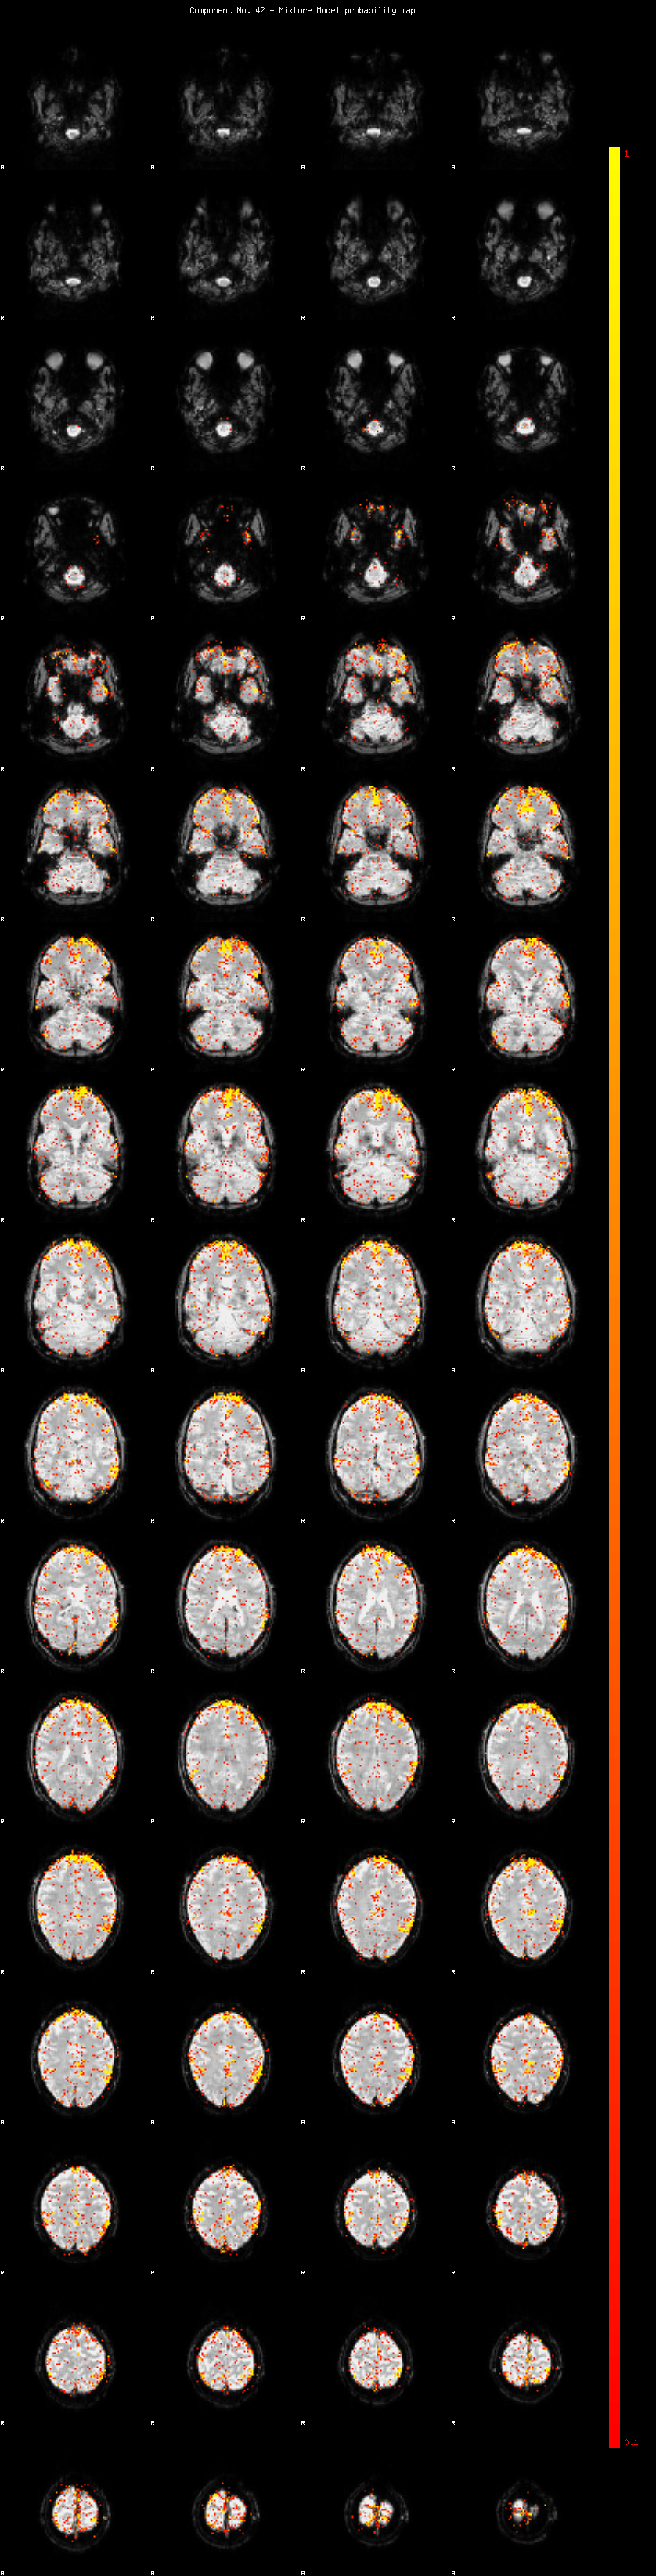

IC_42 Mixture Model fit

Means : -0.000000 3.372374 -2.981275

Vars : 1.000000 5.273786 1.402804

Prop. : 0.944711 0.044439 0.010850